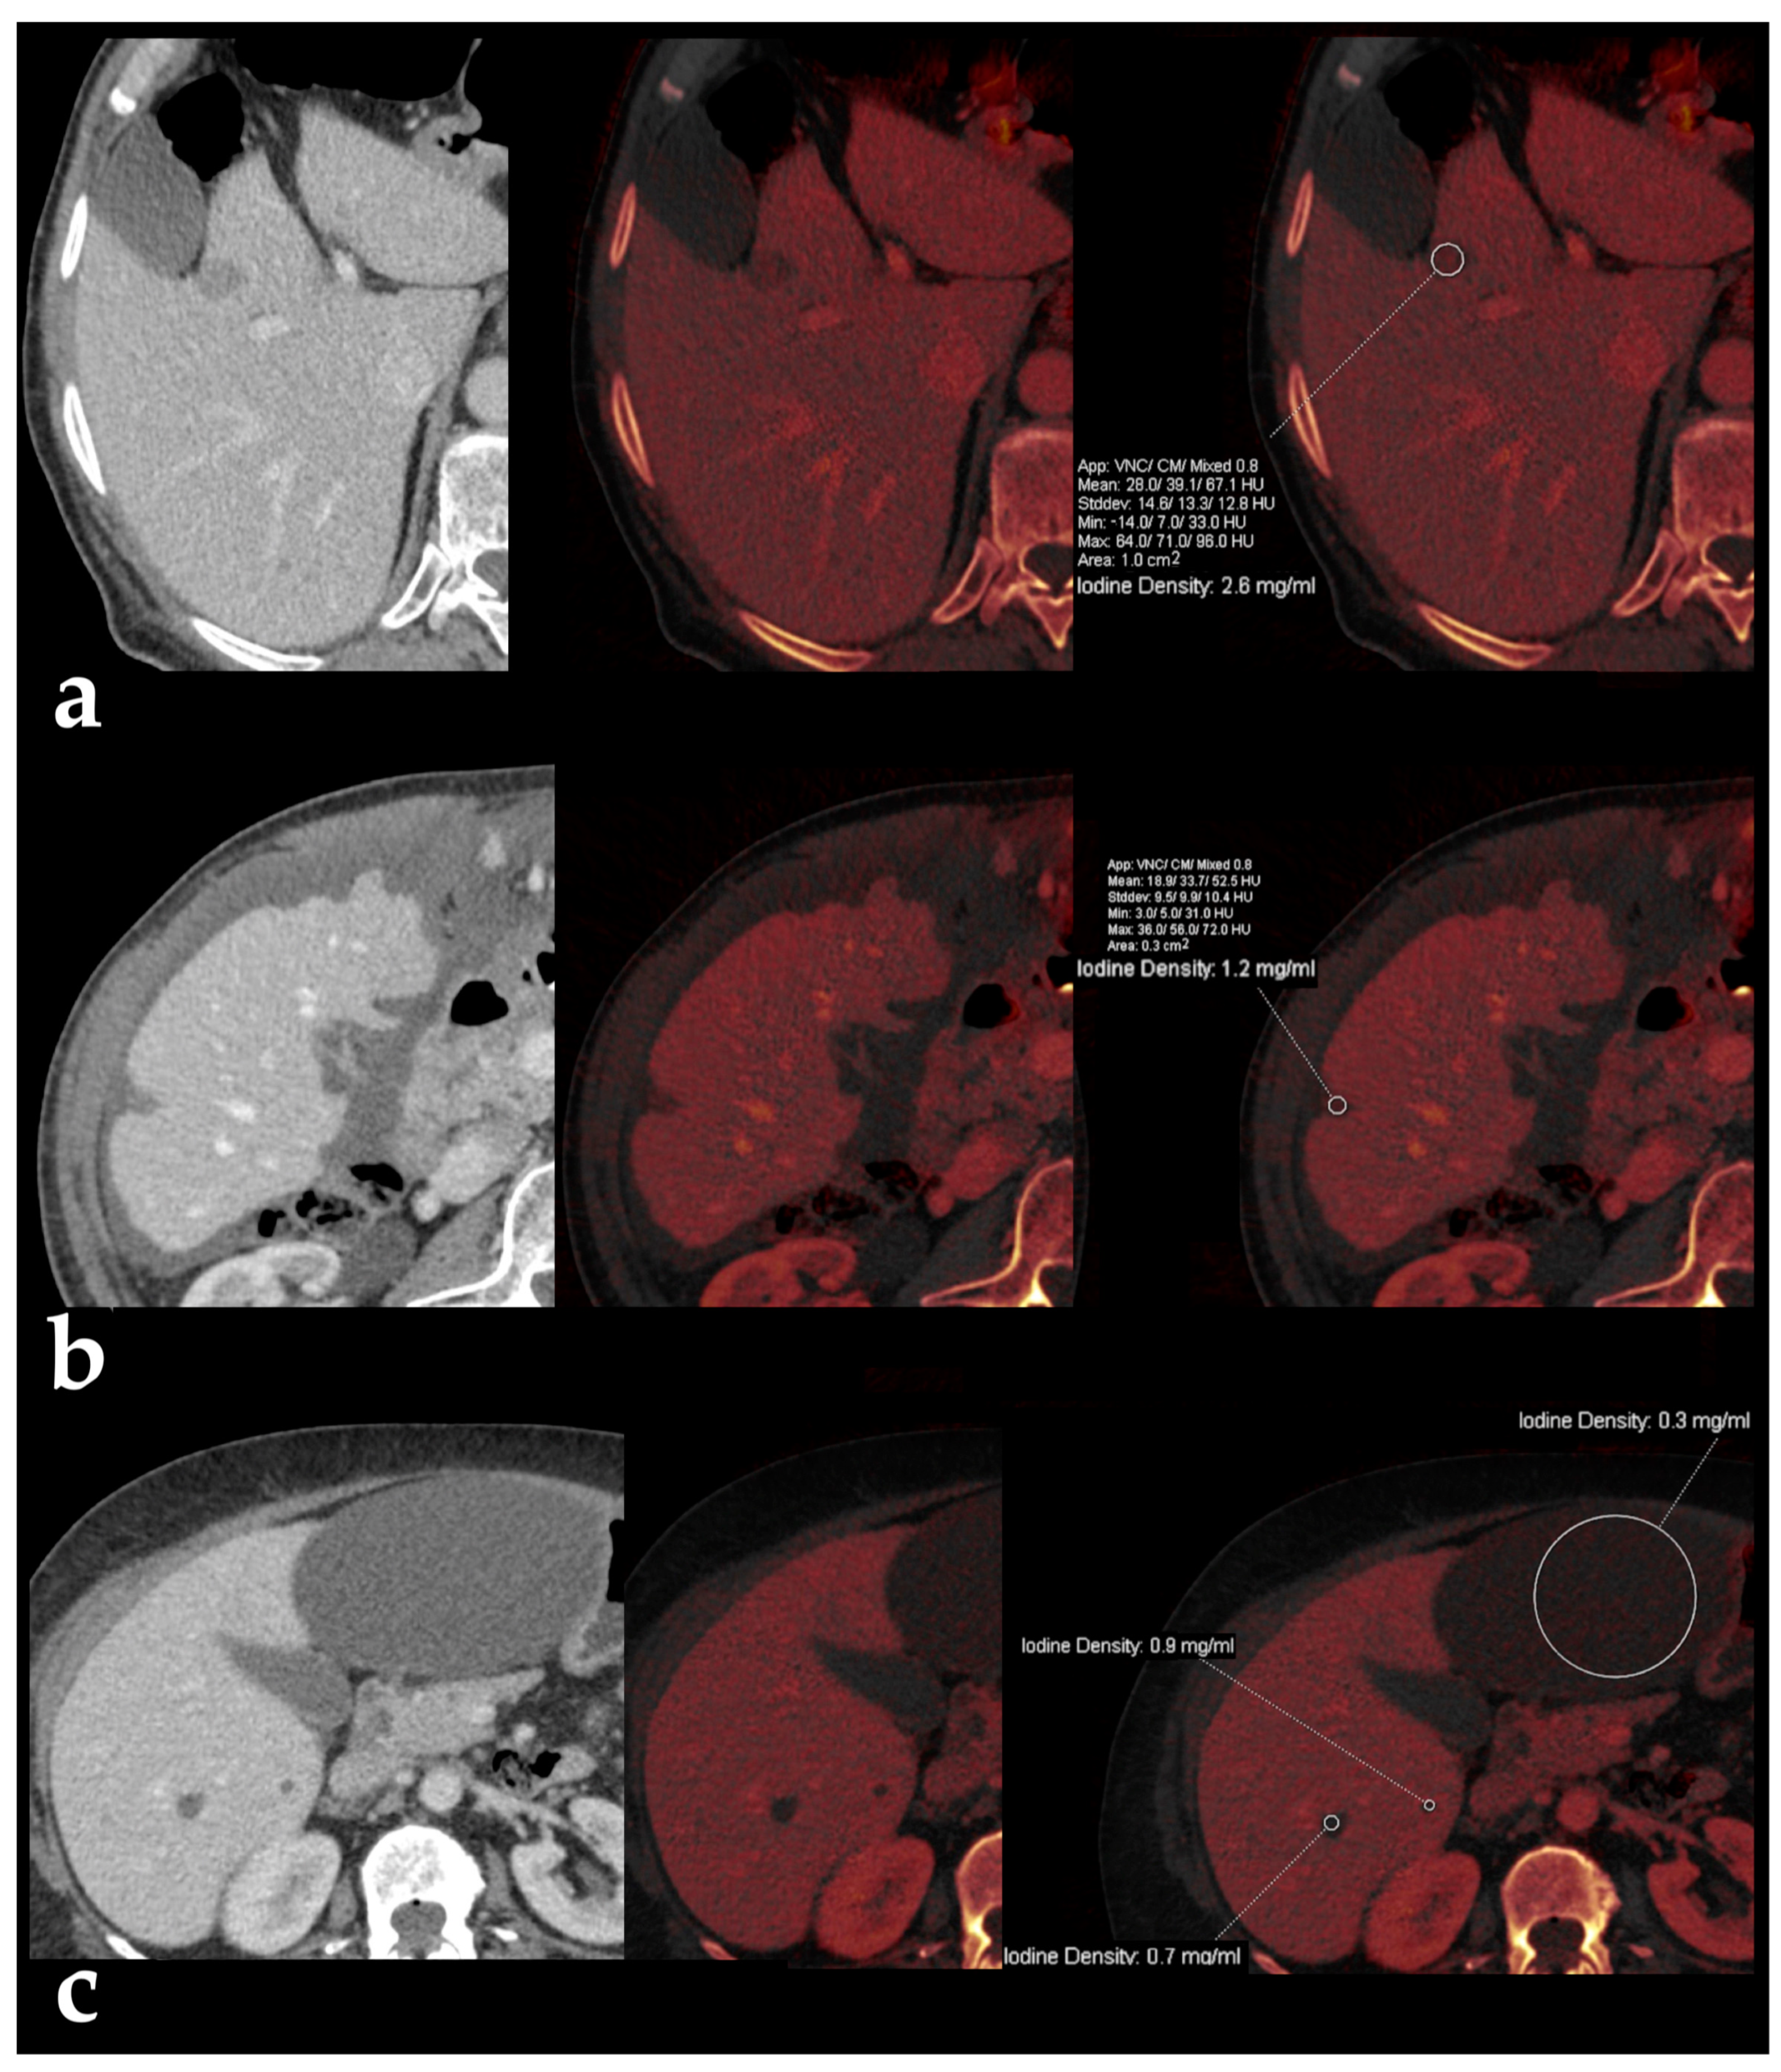

- Sofue, K.; Tsurusaki, M.; Mileto, A.; Hyodo, T.; Sasaki, K.; Nishii, T.; Chikugo, T.; Yada, N.; Kudo, M.; Sugimura, K.; et al. Dual-energy computed tomography for non-invasive staging of liver fibrosis: Accuracy of iodine density measurements from contrast-enhanced data. Hepatol. Res. 2018, 48, 1008–1019. [Google Scholar] [CrossRef]

- Yoon, J.H.; Lee, J.M.; Kim, J.H.; Lee, K.-B.; Kim, H.; Hong, S.K.; Yi, N.-J.; Lee, K.-W.; Suh, K.-S. Hepatic fibrosis grading with extracellular volume fraction from iodine mapping in spectral liver, C.T. Eur. J. Radiol. 2021, 137, 109604. [Google Scholar] [CrossRef]

- Lv, P.; Lin, X.; Gao, J.; Chen, K. Spectral CT: Preliminary studies in the liver cirrhosis. Korean J. Radiol. 2012, 13, 434–442. [Google Scholar] [CrossRef]

- Marri, U.K.; Das, P.; Shalimar Kalaivani, M.; Srivastava, D.N.; Madhusudhan, K.S. Noninvasive Staging of Liver Fibrosis Using 5-Minute Delayed Dual-Energy CT: Comparison with US Elastography and Correlation with Histologic Findings. Radiology 2021, 298, 600–608. [Google Scholar] [CrossRef] [PubMed]

- Morita, K.; Nishie, A.; Ushijima, Y.; Takayama, Y.; Fujita, N.; Kubo, Y.; Ishimatsu, K.; Yoshizumi, T.; Maehara, J.; Ishigami, K. Noninvasive assessment of liver fibrosis by dual-layer spectral detector CT. Eur. J. Radiol. 2021, 136, 109575. [Google Scholar] [CrossRef] [PubMed]

- Nagayama, Y.; Kato, Y.; Inoue, T.; Nakaura, T.; Oda, S.; Kidoh, M.; Ikeda, O.; Hirai, T. Liver fibrosis assessment with multiphasic dual-energy CT: Diagnostic performance of iodine uptake parameters. Eur Radiol. 2021, 31, 5779–5790, Erratum in Eur Radiol. 2021, 31, 8823–8824. [Google Scholar] [CrossRef]